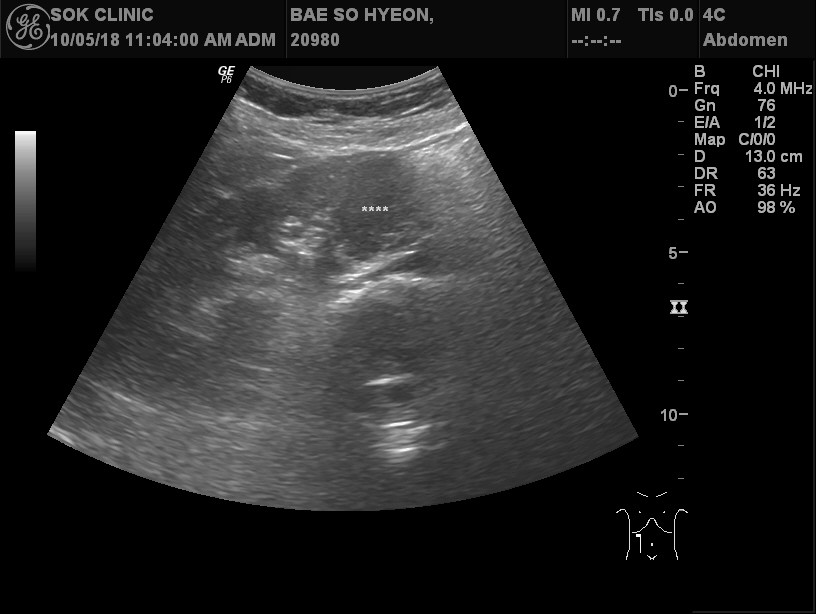

37¼¼ ¿©¼ºÀÌ Àü½ÅÇÇ·Î ¹× µÎÅëÀ» ÁÖ¼Ò·Î ³»¿øÇÏ¿´´Ù.  Æò¼Ò °Ç°­ÇÏ´ø ºÐÀ¸·Î¼­ ¾à ÇÑ´ÞÀüºÎÅÍ ¸Ó¸®°¡ ¹«°Ì°í ÇǷΰ¨ÀÌ À־ ³»¿øÇÏ¿´´Ù.  Ưº°ÇÑ °¡Á··ÂÀ̳ª º´·ÂÀº ¾ø¾ú´Ù. Á¤»ó üÇüÀ̾úÀ¸¸ç Ç÷¾ÐÀÌ 170/110mmHg ·Î  °íÇ÷¾Ð ¼Ò°ßÀÌ °üÂûµÇ¾ú´Ù.  °íÇ÷¾ÐÀÇ ¿øÀÎÀ» ã¾Æº¸±â À§ÇÏ¿© º¹ºÎÃÊÀ½ÆÄ, °©»ó¼± ÃÊÀ½ÆÄ , Ç÷¾×°Ë»ç µîÀ»  ½ÃÇàÇÏ¿´´Ù.  º¹ºÎÃÊÀ½ÆÄ°Ë»ç»ó ¿ìÃø ½ÅÀå¿¡ Àú¿¡ÄÚÇü °áÀýÀÌ °üÂûµÇ¾ú´Ù(±×¸²1).  Á¾¾çÀ» È®ÀÎÇϱâ À§ÇÏ¿© ½ÃÇàÇÑ º¹ºÎCT¿¡¼­µµ ¿ìÃø½ÅÀå¿¡ 5cm Å©±âÀÇ Á¾±«°¡ °üÂûµÇ¾ú´Ù(±×¸²2). ½ÅÀåÁ¾¾çÀ¸·Î ÀÇ½ÉµÇ¾î ¼ö¼ú·Î ½ÅÀåÀ» ÀûÃâÇÏ¿´À¸¸ç Á¶Á÷°Ë»ç»ó ½ÅÀå¾ÏÀ¸·Î È®ÁøµÇ¾ú´Ù.  ¼ö¼úÈÄ Ç÷¾ÐÀº 100/60 À¸·Î Á¤»óÈ­µÇ¾î Ç÷¾Ð¾àÀº Áß´ÜÇÏ¿´´Ù.

÷ºÎÆÄÀÏ 1 : RCC_sono.jpg